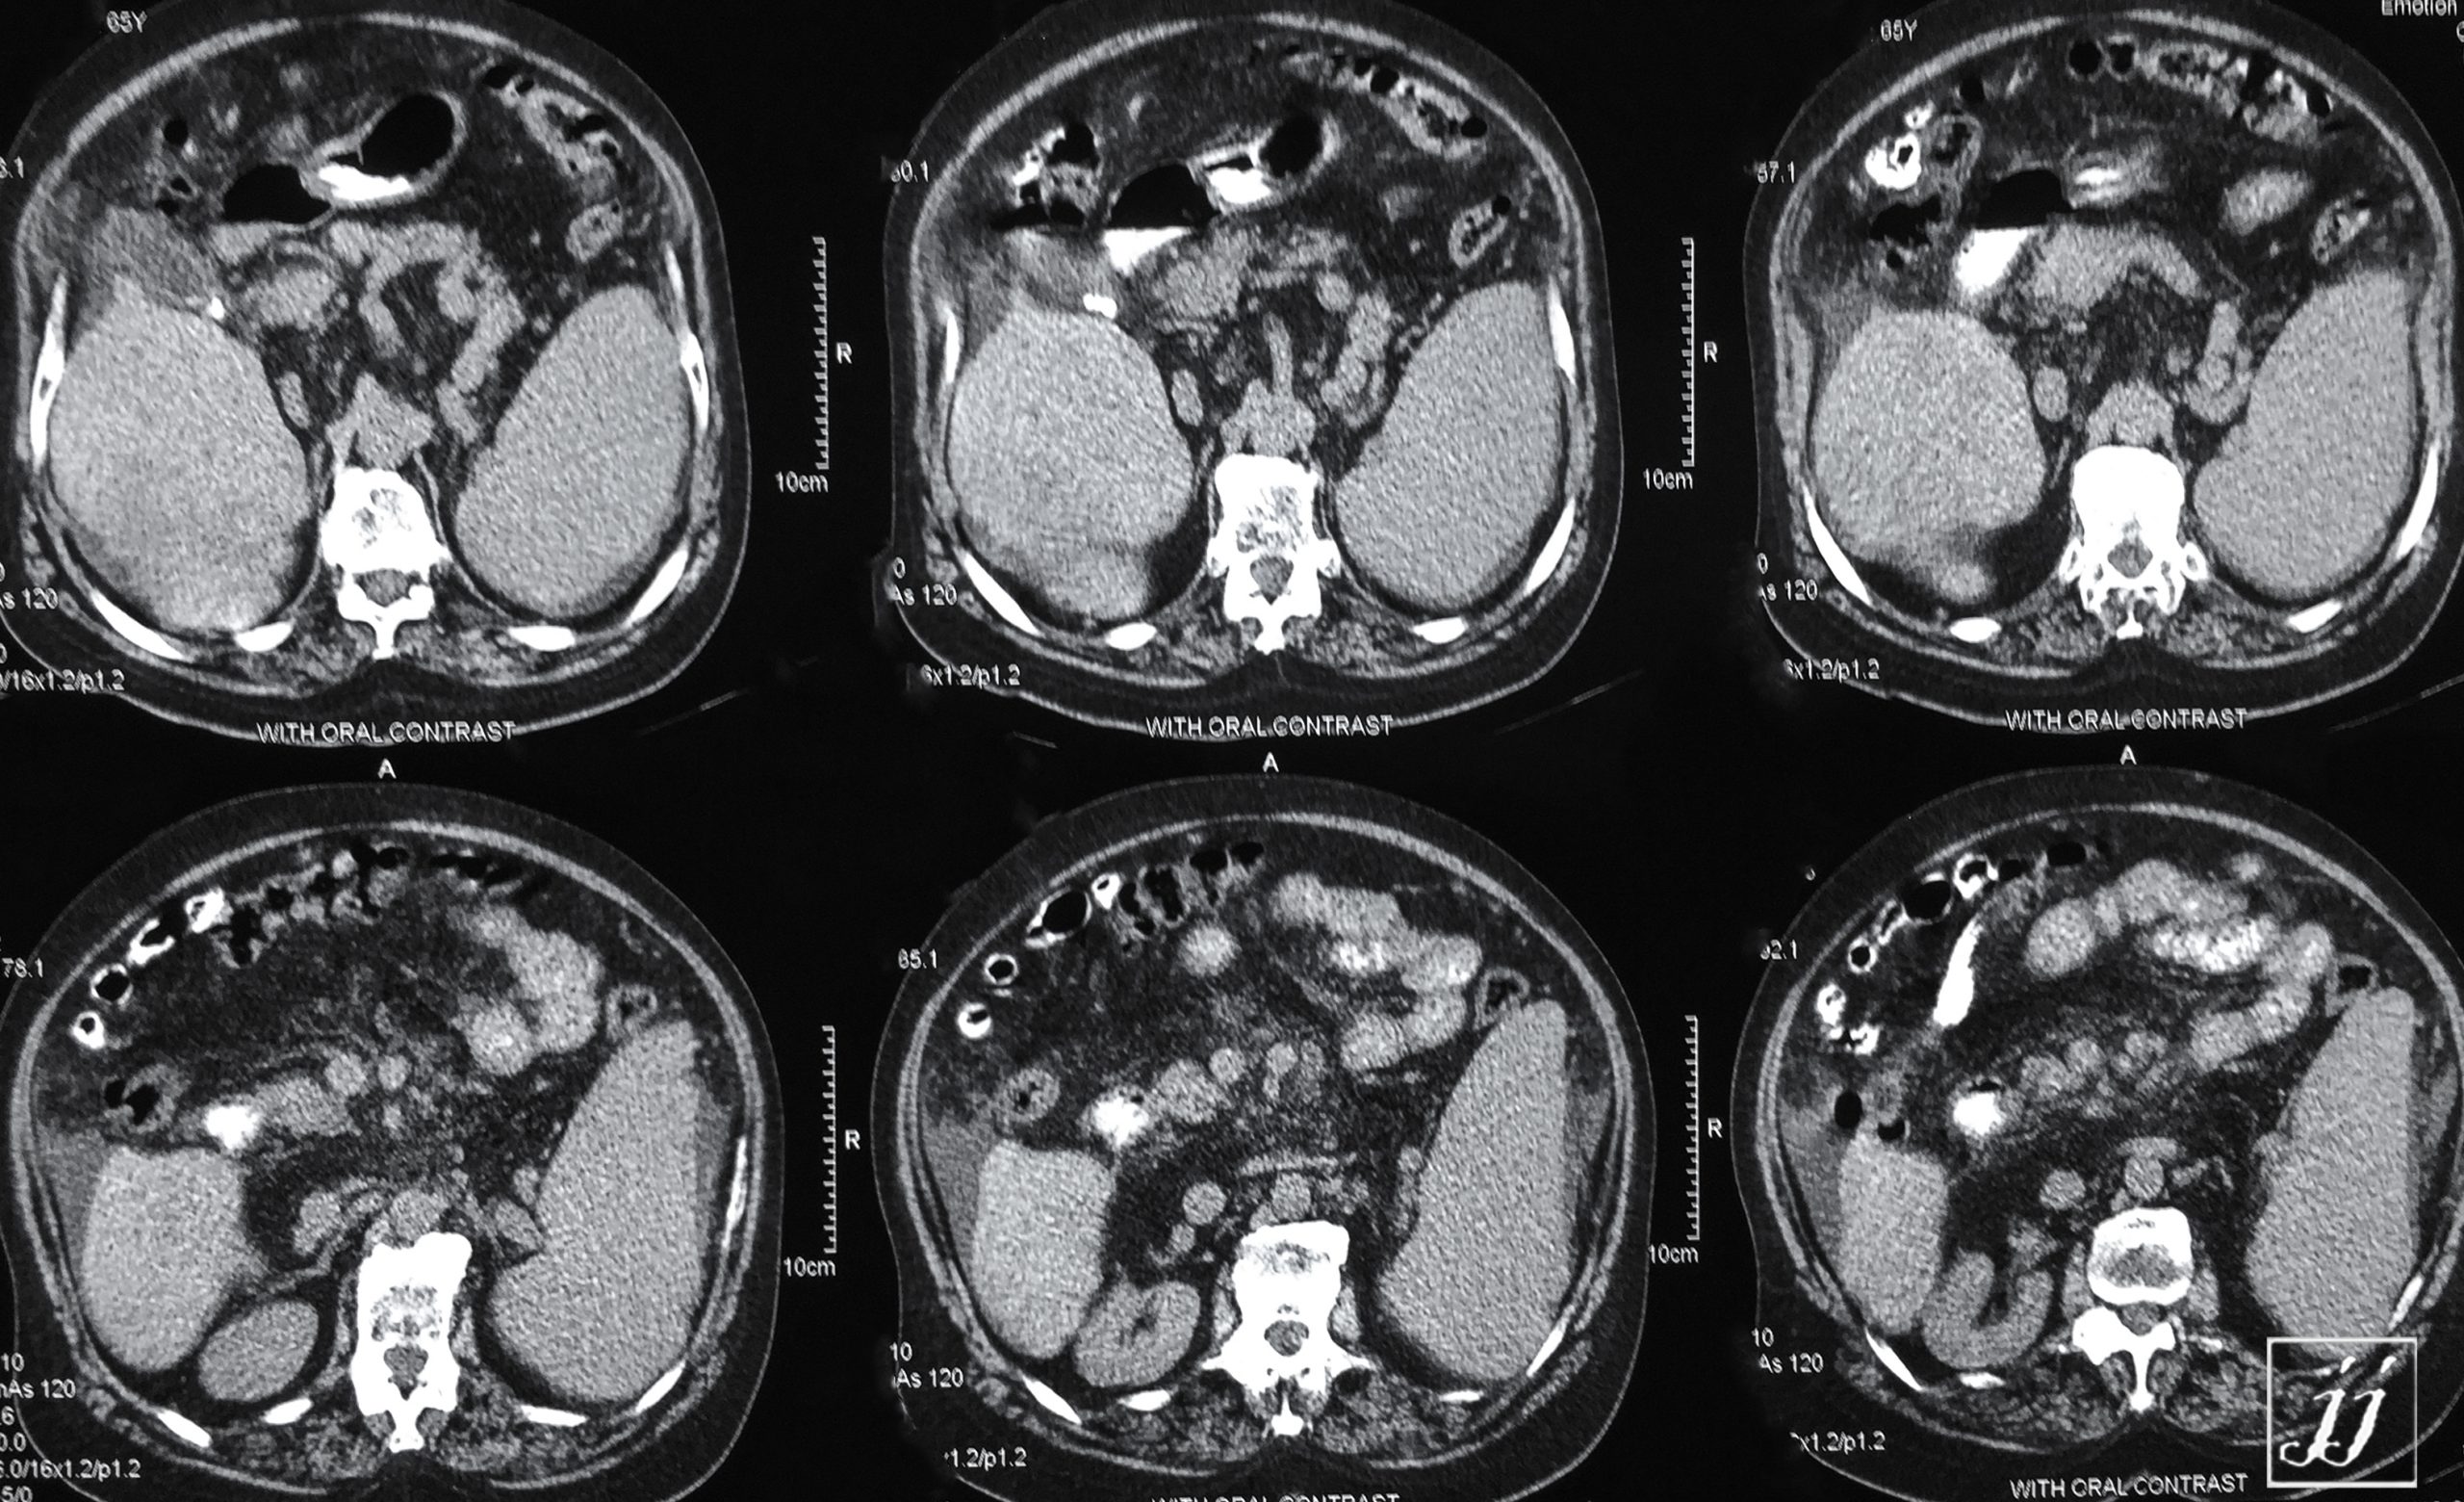

Abdomen- Ascites and thick gall blad (2)